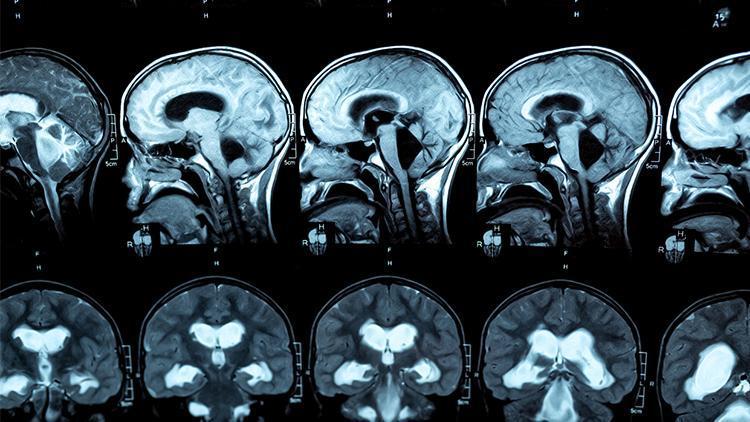

Ancak Doktor Mitchell, hastanın zihinsel durumunu daha iyi değerlendirmek için bir CT taraması istedi. Bunun ise aslında somut bir sebebi yoktu. Elizabeth Mitchell, hastayı daha detaylı değerlendirmesi gerektiğine neden karar verdiğini, “Aslında tanımlanamayacak bir şey. 20 yıllık deneyimin verdiği bir şey ya da bir içgüdü” sözleriyle anlattı.

Tarama sonuçlarına bakarken Mitchell’in nefesi kesildi. Daha önce hiç böyle bir şey görmediğini söyleyen doktor, meslektaşlarını topladı ve sonuçlara tüm acil servisteki uzmanların bakmasını istedi.

O anları, “Sessiz kaldım. Tek düşünebildiğim şey şuydu; kimse bunu bunca zamandır nasıl anlayamadı?” sözleriyle anlatan Mitchell, Chloe’nin annesiyle konuştuktan sonra bu sorunun zihninde daha derinden yankılandığını söyledi.

Acil servis doktoru Elizabeth Mitchell, kısa bir muayene ile göndermek istemediği Chloe’ye çeşitli testler ve CT taraması yaptı.

Tarama sonuçlarını görünce şoke olan Mitchell, bomba gibi bir haber vermek için hemen Chloe’nin ailesini aradı. Chloe, Mitchell'in "Gördüğüm en şiddetli hidrosefali vakası" olarak nitelendirdiği hayatı tehdit eden bir duruma sahipti ve olabilecek en kısa sürede bir beyin ameliyatına ihtiyacı vardı. Mitchell, Chloe’yi acil şekilde yoğun bakım ünitesine yönlendirdi.

Halk arasında ‘beyindeki su’ olarak bilinen hidrosefali, beyin omurilik sıvısının ventrikül olarak bilinen boşluklarda birikmesinden kaynaklanıyor. Hidrosefali kısaca, beyin omurilik sıvısının çoğalmasıyla, beyin karıncıklarının, kimi zaman da kafatasının büyümesine yol açan bir hastalık olarak tanımlanıyor. Beyin omurilik sıvısı, çok çeşitli beyin işlevleri için kritik bir öneme sahiptir.

Chloe’nin de durumu oldukça ciddiydi. Fazla sıvı, beynin hafıza, karar verme ve duygudan sorumlu ön loblarını Chloe'nin kafatasının içine sıkıştırıyordu.

Mitchell, “Yıllar boyunca kimsenin CT taraması yapmadığına inanamıyorum. Bu gerçekten oldukça tuhaf” dedi.

Chloe’ye MRI (Manyetik Rezonans Görüntüleme) taraması yapıldı. Bu tarama sonucunda ise Chloe’nin hidrosefalisinin, ventriküller arasında tıkanmaya neden olan bir daralma olan akuaduktal stenozdan kaynaklandığını belirlendi.